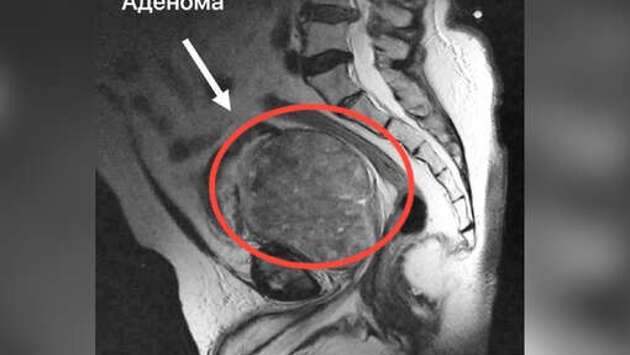

Врачи Можайской больницы и Московского областного научно-исследовательского клинического института имени М.Ф. Владимирского (МОНИКИ) спасли 71-летнего мужчину с простатой, увеличенной в 20 раз. Об этом сообщает минздрав Московской области. Пациент обратился к врачам с жалобами на острые боли и затрудненное мочеиспускание. Они оказались вызваны аденомой предстательной железы, которая сдавливала мочевой пузырь. Объем простаты был в 20 раз больше нормы. Мужчине экстренно провели прокол мочевого пузыря и установили цистому - трубку для вывода мочи через искусственное отверстие в брюшной полости. Операция прошла успешно и заняла около получаса, после чего пациента направили в МОНИКИ. "Мы провели лапароскопическую операцию, во время которой, не вскрывая мочевой пузырь, получили доступ к предстательной железе и удалили увеличенную в размерах аденому простаты. Операция заняла 3,5 часа. Гистология показала, что опухоль была доброкачественной", – рассказал руководитель отделения урологии МОНИКИ Алексей Подойницын. Пациента выписали в хорошем самочувствии.